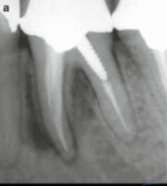

Root Canal Treatment (RCT)

Endodontic treatment to remove infected pulp.

fractured tooth

root canal if into pulp

vitality test if no pulp availible

can repair with bonding or crown.

root fracture

vertical or horizontal

outcome depends on location and mobility

mobility means extract